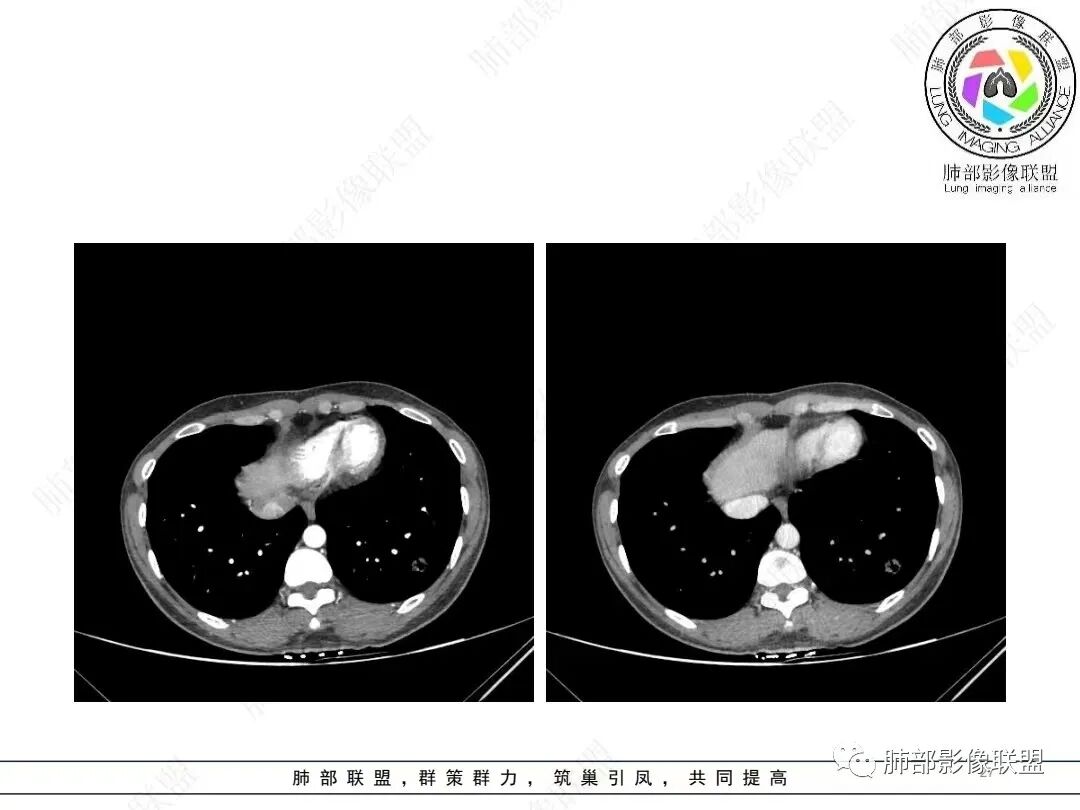

肺动脉供血

@张明辉临沂市人民医院 今天病例粗大肺动脉供血+空洞结节,和我上传病例比较像。

2、影像特点:左肺下叶类圆形结节影,周围可见多发细小毛刺,浅分叶,张力不高,未见胸膜牵拉。病灶内隐约见空泡影(未提供CT值),近端部分血管呈杵状增粗,可疑脐凹征。增强后实性部分有轻度强化。外围病灶,与支气管关系不明确。